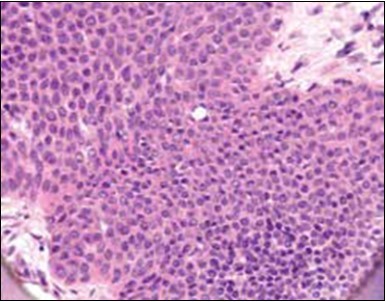

Granular arrangement of malignant cells and intercellular bridges are conspicuous with the demonstration of nuclear atypia, pleomorphism, prominent mitosis and tumour necrosis. A peripheral palisade is discernible within the cellular aggregates. Mitotic figures are common and can be quantified as up to 12 mitosis/ high power field. Tumour differentiation can prominently be of the ductal category with the demonstration of intra-cytoplasmic lumina. Comedo type tumour necrosis is evident along with foci of squamous differentiation The neoplasm is reactive to periodic acid Schiff ‘s (PAS) stain. (Figure 1, Figure 2, Figure 3, Figure 4, Figure 5, Figure 6, Figure 7, Figure 8, Figure 9, Figure 10, Figure 11, Figure 12, Figure 13.

Figure 4.Cellular atypia, mitosis and focal necrosis in eccrine porocarcinoma(16).